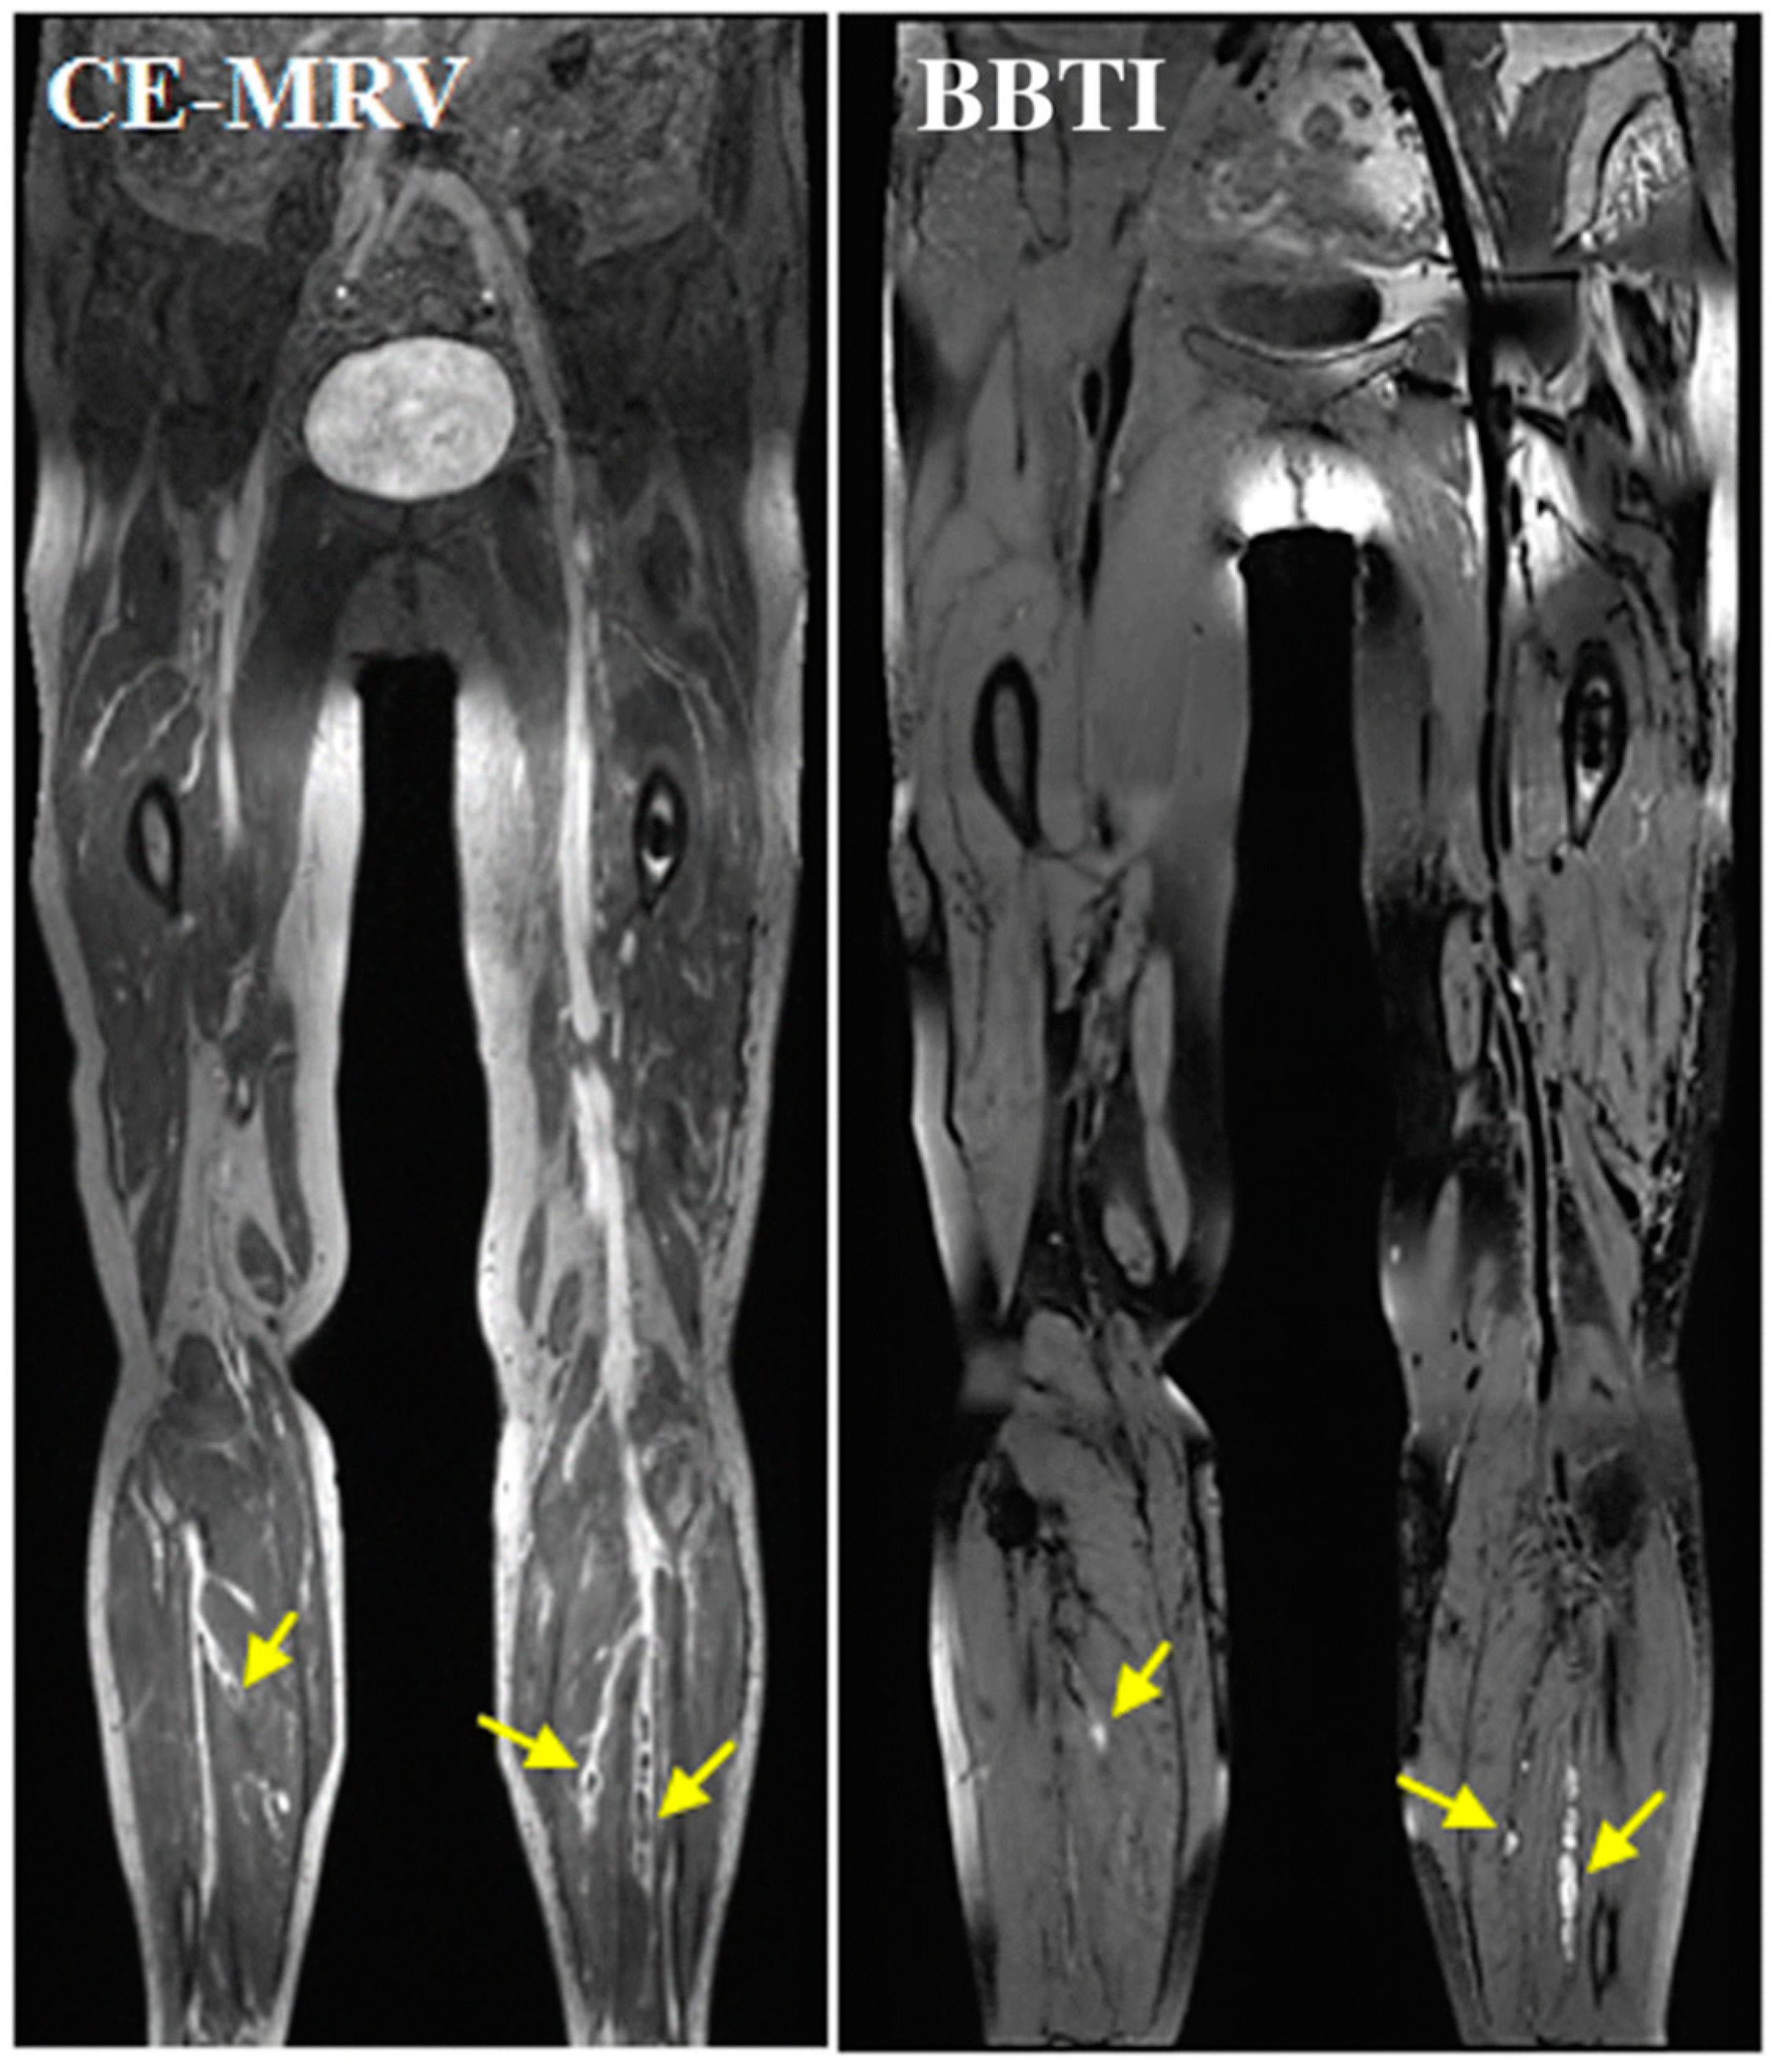

- Chen, H.; He, X.; Xie, G.; Liang, J.; Ye, Y.; Deng, W.; He, Z.; Liu, D.; Li, D.; Liu, X.; et al. Cardiovascular magnetic resonance black-blood thrombus imaging for the diagnosis of acute deep vein thrombosis at 1.5 Tesla. J. Cardiovasc. Magn. Reson. 2018, 20, 1556. [Google Scholar] [CrossRef]

- Andia, M.E.; Saha, P.; Jenkins, J.; Modarai, B.; Wiethoff, A.J.; Phinikaridou, A.; Grover, S.P.; Patel, A.S.; Schaeffter, T.; Smith, A.; et al. Fibrin-Targeted Magnetic Resonance Imaging Allows In Vivo Quantification of Thrombus Fibrin Content and Identifies Thrombi Amenable for Thrombolysis. Arterioscler. Thromb. Vasc. Biol. 2014, 34, 1193–1198. [Google Scholar] [CrossRef]